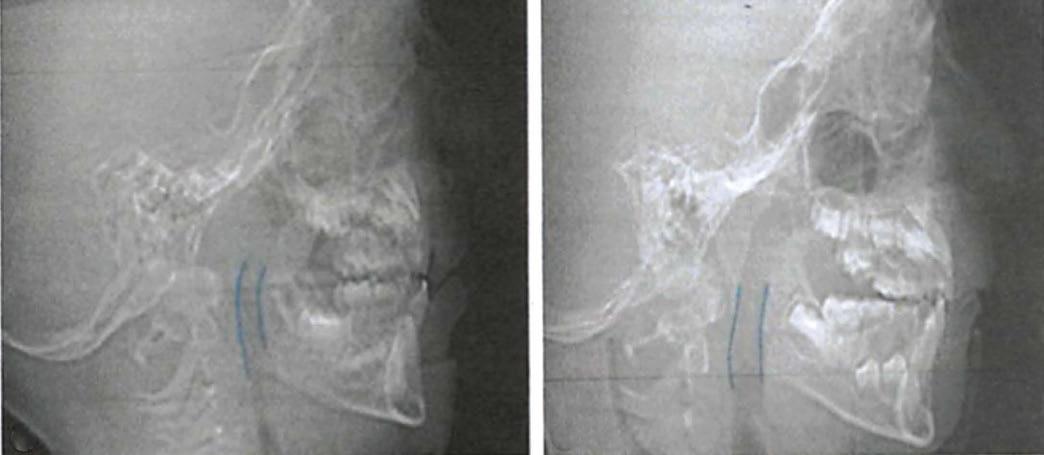

Figure 1: Cephalometric X-rays of patient in the primary dentition pre- and post-Orthotropics® treatment showing airway improvement sufficient to eliminate OSA per PSGschool, and is an aggressive tennis player at age 17. Clearly, he is one of the lucky ones whose problem was resolved before he sustained brain damage, which might have affected his academic performance, motor coordination, and overall health.

The panoramic X-ray showed a full complement of teeth, a left horizontally impacted third molar, along with the three other third molars (Figure 2F). The pretreatment cephalometric analysis revealed a skeletal Class II measurement of an ANB of 6.8° with a retrognathic mandible measuring aSNB of 76.6°. The mandible had a hyperdivergent growth pattern of 58.35% with a long anterior face height of 130.6 mm (Figure 3A). The maxillary incisors showed protrusion of .9.5mm to APOg with a proclination of 115.8°, while the mandibular incisors were retrusive with an APOg mea surement of .4 mm and retro clined to 84°.